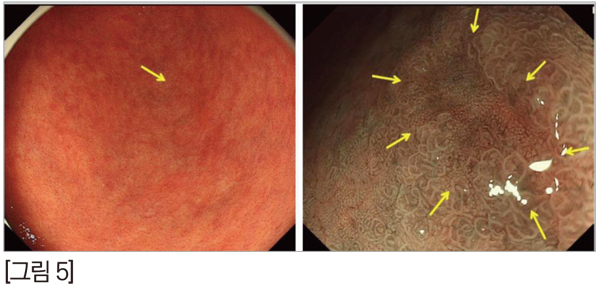

케이스를 보겠습니다. 첫번째 케이스는 미니핀, 중성화한 수컷이고, 2003년생 5kg입니다. 구토를 주 증상으로 내원하였습니다. 혈액검사상 미약한 저알부민혈증과 빈혈 이외에는 큰 특이사항이 없었습니다. [그림 7]

방사선 검사에서도 큰 이상이 없어서 초음파 검사를 진행하였습니다. [그림 8]